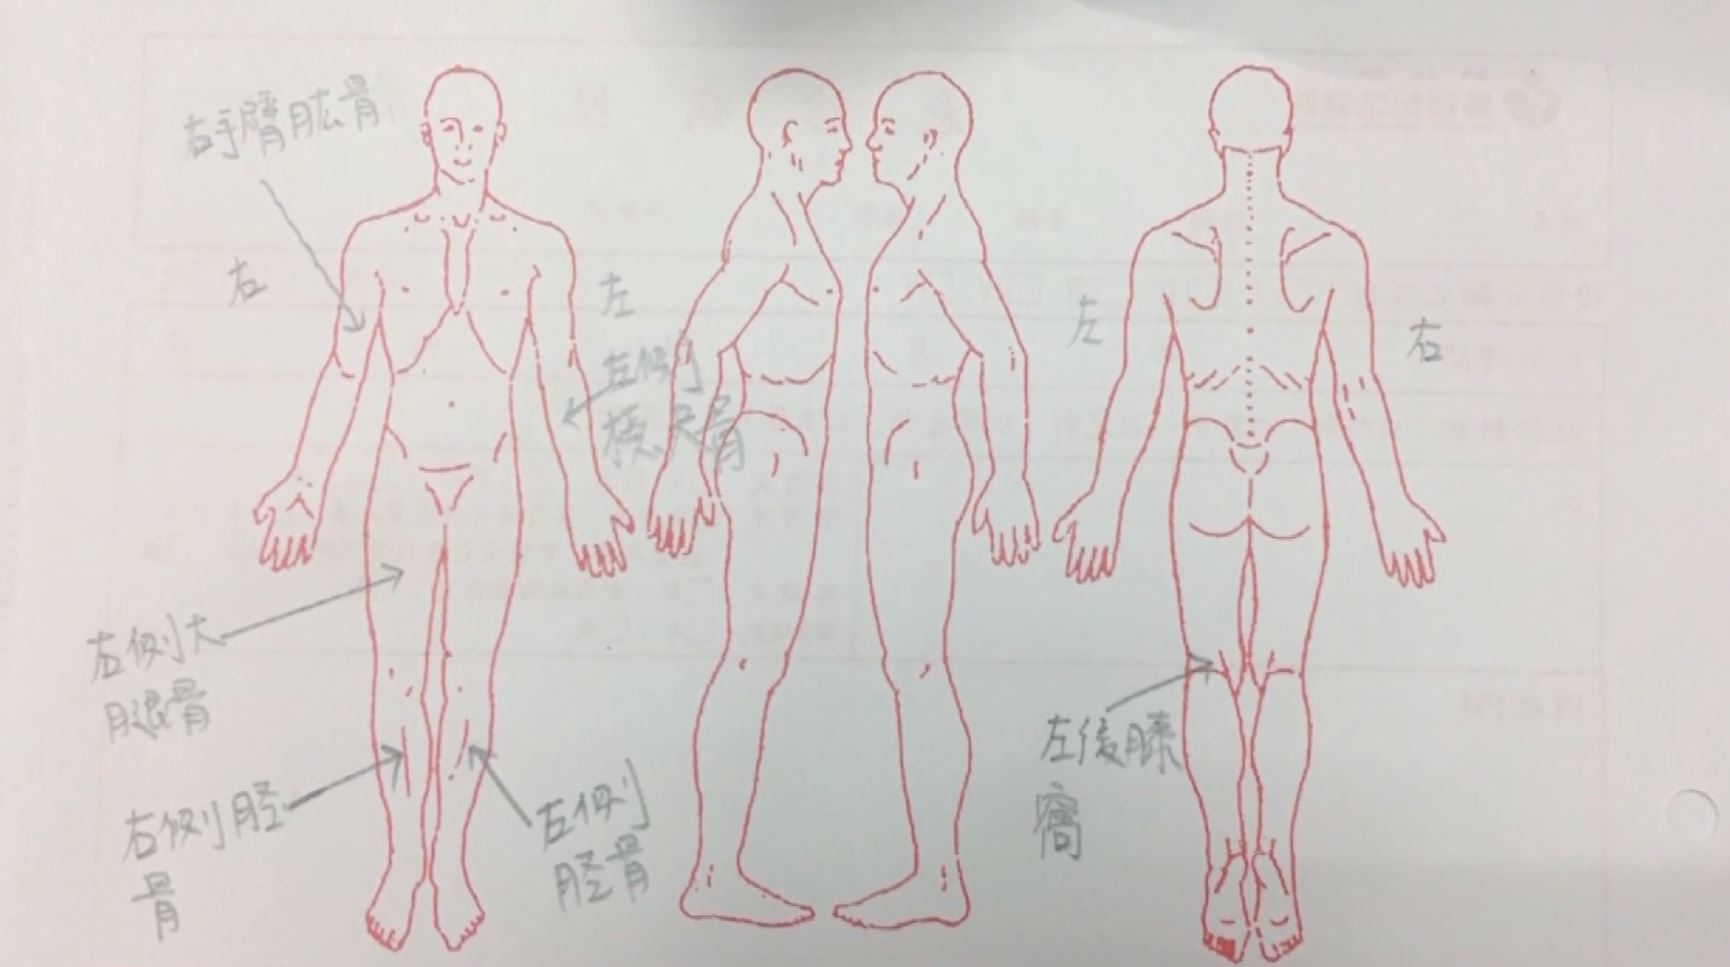

▼男嬰四肢有骨折新舊傷。(圖/翻攝畫面)

直到去年5月,狠父再度施暴,在男嬰的左膝內側留下長達8公分的撕裂傷,造成他血流不止,父母驚覺事情不妙,才趕緊帶他到醫院。為恭醫院泌尿科主治醫師李之微為4個月大的男嬰治療,赫然發現除了左膝內側外,他身上還有其他傷口,甚至已生出新的組織,一問母親卻得不到清楚答案,父親也含糊其辭,李之微隨即通報家暴。未料之後進一步檢查,他更發現男嬰左手尺骨、雙側股骨、右腿脛骨都有骨折舊傷,小小嬰孩竟承受如此大的折磨,讓李之微痛批男嬰父親「根本枉為人父!」

▼(圖/東森新聞)